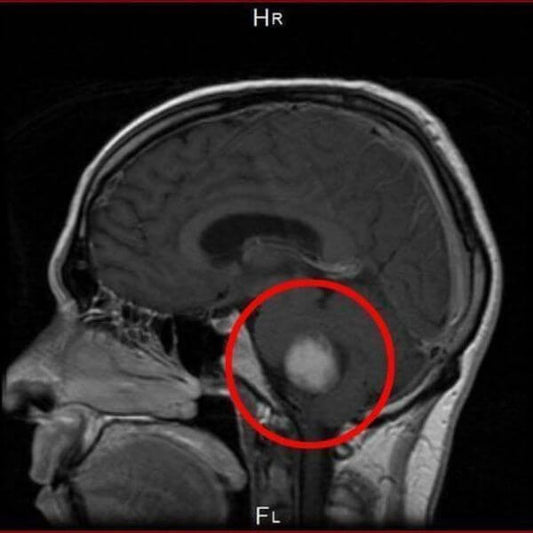

There's a clear cell phone-cancer link, but FDA...

A recent study by the National Toxicology Program/National Institutes of Health (NTP/NIH) shows clear evidence of a causal link between cancer and exposure to wireless cell phone signals. Results from the $30...